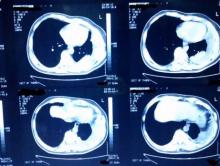

In organized stage 3 pleural effusions, the thickened visceral pleural layer entraps and collapses the lung resulting in lung volume loss with crowding of the intercostal spaces. The patient is a 56-year-old male previously treated for pulmonary tuberculosis with a left pleural effusion. A 4 cm single incision for thoracoscopy through the 4th intercostals space in the anterior axillary line was performed with removal of the segment of the rib along the wound to provide adequate space for surgery. The single incision technique with rib segment excision minimizes intercostal nerve injury in the crowded rib space compared with use of multiple ports. After gaining access to the pleural cavity, the fibrinous debris in the pleural space is evacuated to provide adequate space for dissection and good view of the thick visceral pleura trapping the lung. Identification of the correct plane between the organized pleura and lung parenchyma is key to the safe conduct of thoracoscopic decortication. Decortication is done using blunt end of suction tip, a swab, and a peanut mounted on curved ring forceps. Once the lung is completely mobilized, the thickened organized pleura is excised and hemostasis along the chest wall is attained. At the end of the procedure, warm saline lavage of the pleural cavity is done along with manual bagging of the lung to check for lung expansion and air leak. Two chest drains are placed, directed anteriorly and posteriorly, with the drains exiting from edges of the skin incision. The patient was discharged in the morning of the 5th postoperative day with the chest x-ray showing well expanded lung.